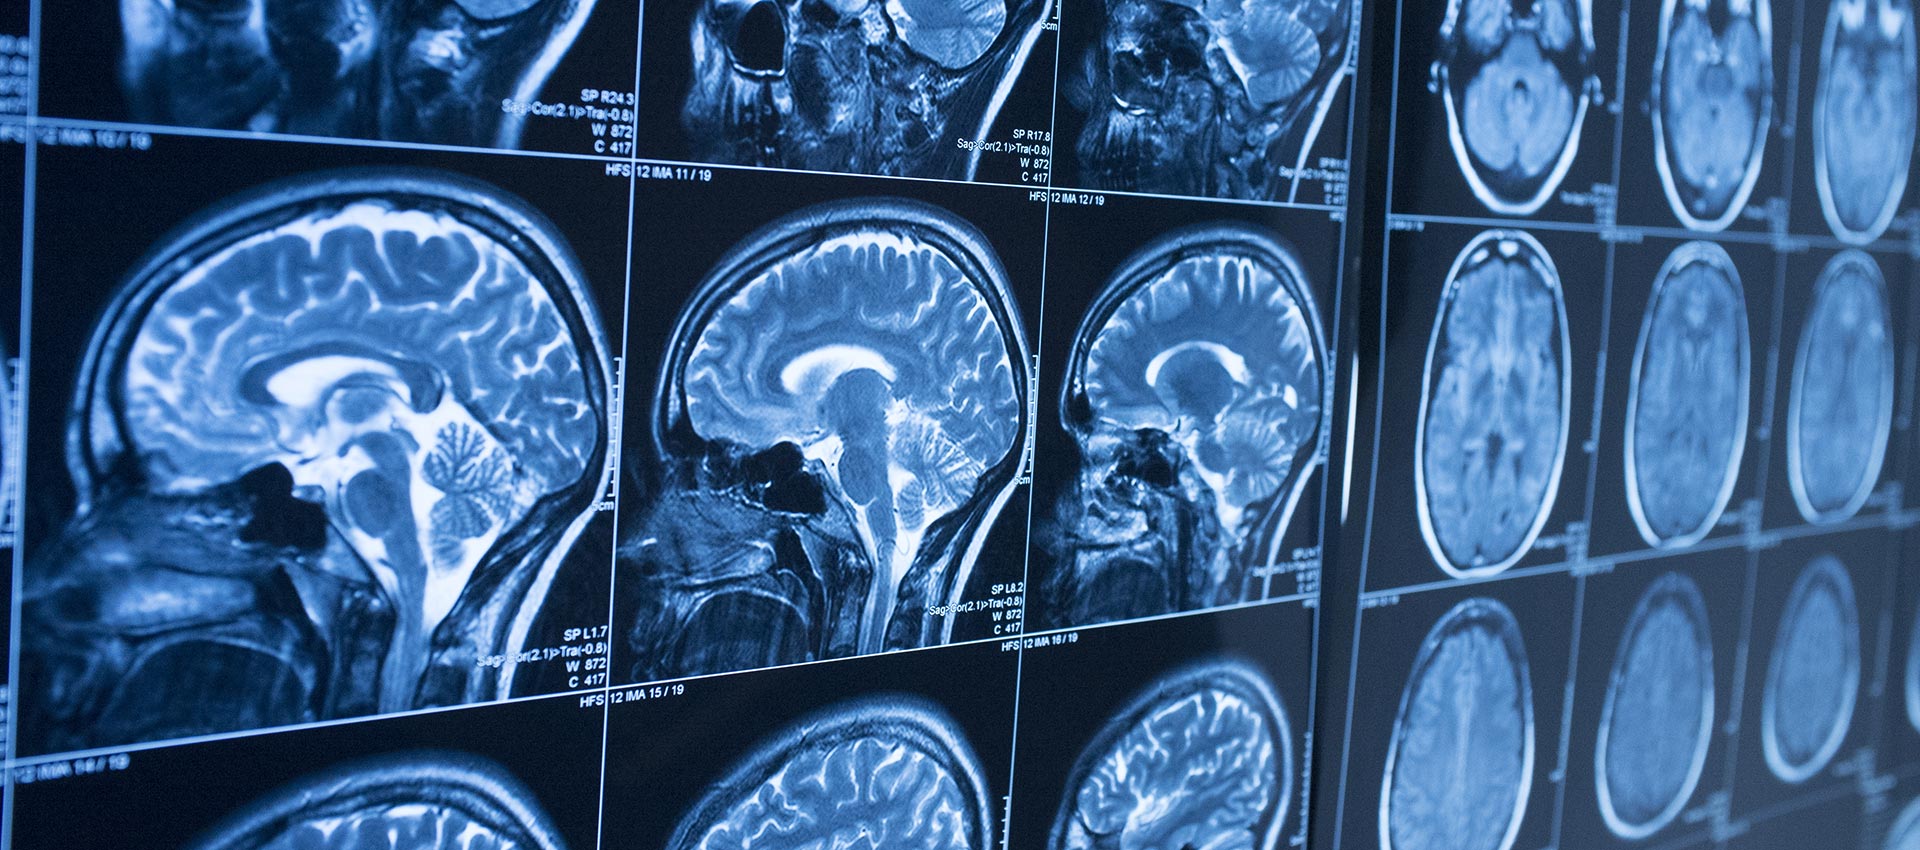

Magnetic Resonance Imaging (MRI) is a safe, non-invasive exam that uses powerful magnets and advanced technology to create highly detailed images of the body. Unlike X-ray or CT imaging, MRI does not use radiation, making it an excellent tool for evaluating a wide range of conditions.

MRI is commonly used to diagnose and evaluate:

- Stroke, aneurysms, and neurologic conditions